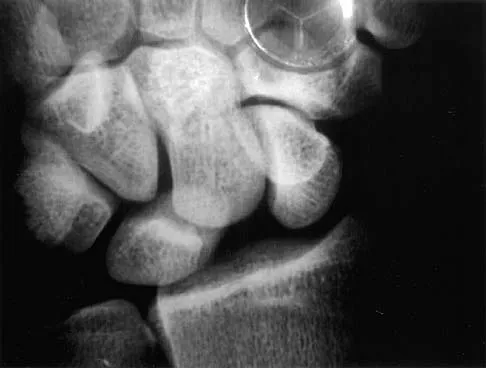

Question 66

A 23-year-old woman sustains an injury to her right hand after falling off her snowboard. Examination reveals that she has difficulty moving her fingers. A radiograph and a clinical photograph are shown in Figures 8a and Figure 8b. Management should consist of

Explanation